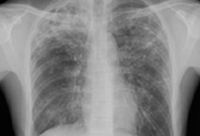

Radiografía de tórax que muestra la hiperinflación en un paciente con EPOC. El tórax distendido es causado por el componente enfisema de la EPOC, en lugar de por la bronquitis crónica, que subyace los síntomas de tos

De la colección personal del Dr. M. A. Sharifabadand, SUNY en Stony Brook School of Medicine, Departamento de Medicina Intensiva y Pulmonar, Mineola, Nueva York y el Dr. J. P. Parsons, The Ohio State University Medical Center, Columbus; usado con autorización